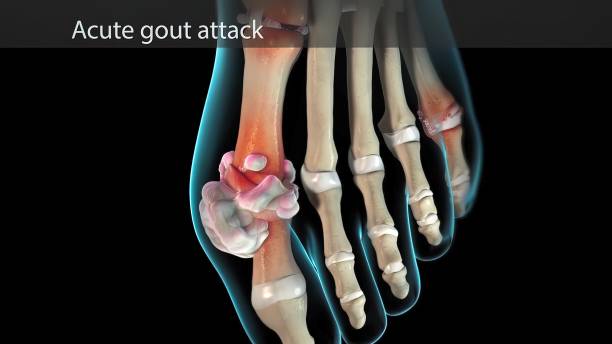

급성 통풍 발작

급성 통풍 발작은 갑작스럽게 발생하며, 대개 하루 이내에 최대 발생점에 도달합니다. 발작이 발생하면 통증이 극심하게 시작되고, 발적 부위는 붉고 따끔거리며 따끔거리고, 적출물로 인해 부어오릴 수 있습니다.

염증

급성 통풍 발작은 관절 내부에서 염증이 발생합니다. 이는 염증을 일으키는 화학 물질이 적출물로 발적 주위에 축적되기 때문입니다. 염증은 일반적으로 통증, 붓기, 붉어짐 등을 초래할 수 있습니다.